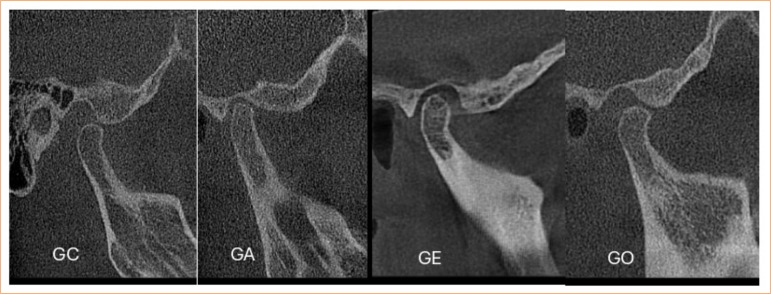

Methods: Eighty images of the jaw condyle with three types of degenerative diseases, flattening, osteophytes, erosion and control group were analysed, obtained through CBCT. The analyses were carried out through texture analysis with three regions of interest (ROIs) corresponding to specific bone sites. The scans were exported to MaZda software, in which the ROIs were delimited following previously marked contours, and the co-occurrence matrix values were calculated for selected texture analysis parameters.